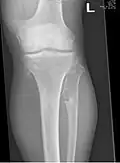

-

Multiple osteochondromas around the knee -

The diagnosis of HMO is based upon establishing an accurate correlation between the above-mentioned clinical features and the characteristic radiographic features. Family history can provide an important clue to the diagnosis. This is supplemented by testing for the two genes in which pathogenic variants are known to cause HMO namely EXT1 and EXT2. A combination of sequence analysis and deletion analysis of the entire coding regions of both EXT1 and EXT2 detects pathogenic variants in 70–95% of affected individuals.[3][7] The hallmark of radiographic diagnosis is the presence of osteochondromas at the metaphyseal ends of long bones in which the cortex and medulla of the osteochondroma represent a continuous extension of the host bone. This is readily demonstrable in radiographs of the knees.[3][1]